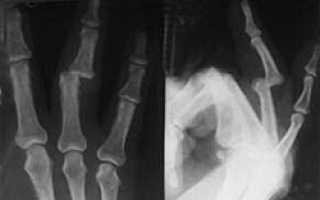

Оперативное лечение не устраняет всех последствий длительно существовавшего смещения оснований пястных костей, но значительно улучшает состояние. При давности вывихов свыше 4-5 месяцев ограничиться только открытым вправлением невозможно, и требуется артродез с удалением неполноценного суставного хряща с концов основания пястных костей и костей запястья (рис. 73). При вывихах большой давности и значительном смещении пястных костей артродез возможен только при их укорочении. Всегда необходима ретроградная внутри- и чрескостная фиксация спицами запястно-пястных соединений.